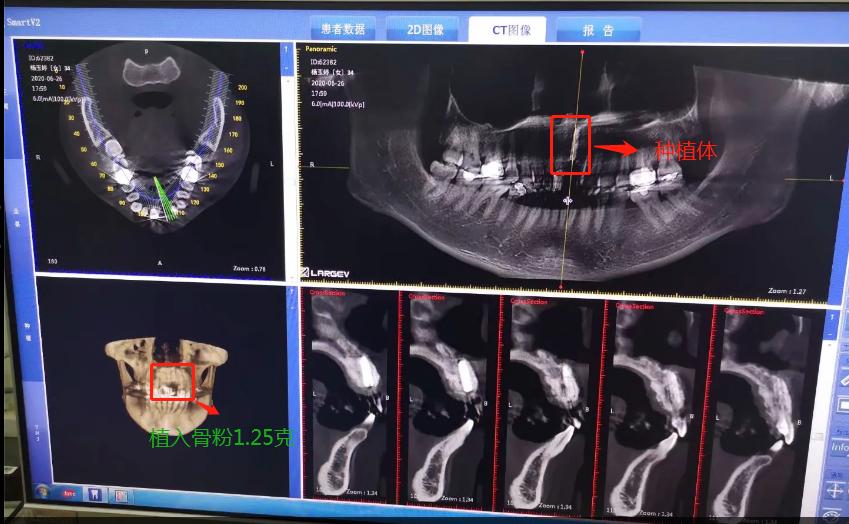

植入种植体后拍的CT

2020年6月26日,终于等到了,我要种植了牙根啦,我牙根弄了法国安卓建品牌的种植体,之前还去几家口腔门诊和烈士陵园的光华口腔也咨询过和对比价格,瑞士ITI品牌太贵了(还有别的品牌M美国皓圣、韩国登腾、德国ICX、瑞典诺贝尔等),本来选美国皓圣,但我的是门牙,要选材质比较好,考虑美观问题,最后选择中等价位的安卓健。手术很快,而且伤口不是很大,我四天就康复,做完当下就可以说话,完全没有阻碍。因为牙根种进去必须要等半年时间跟我骨头长在一起,因为我当时做手术的时候种植入的骨粉还是软的,还没有变成硬骨头。现在的阶段是等待上基台,上完基台半个月时间上牙冠。2020年12月26日上基台。预计要2021年1月份可以全部完成种牙过程,期待着我带上牙齿的那一刻。